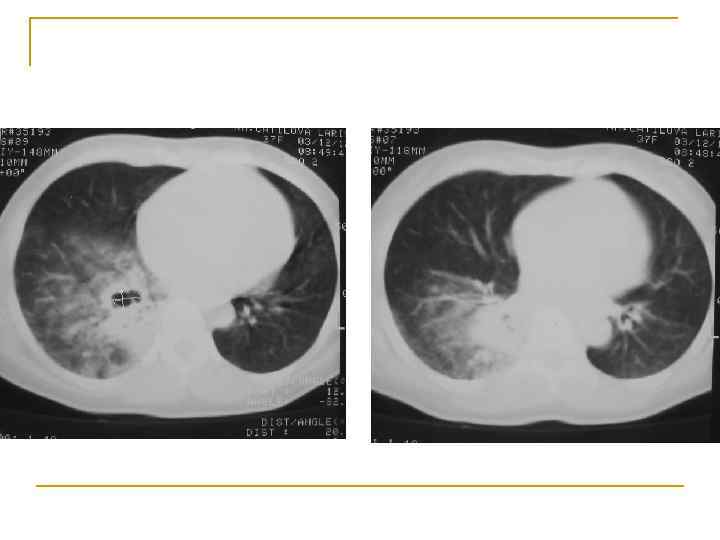

Investigaţii paraclinice Bronhoscopia: se poate ajunge până la bronhiile subsegmentare şi se poate vizualiza leziunea cu aprecierea caracterului şi răspândirii procesului. Este posibilă biopsia tumorii (inclusiv prin periaj) cu examenul histologic al fragmentelor de biopsie sau al aspiratului bronşic. Rezultat morfologic în peste 90% cazuri de cancer central. Examenul citilogic al sputei sau al spălăturilor bronşice: este pozitiv la 90% dintre pacienţii cu cancer central şi în 50% cazuri de cancer periferic. Tomografia computerizată: permite depistarea tumorii în 95%. Ea permite determinarea răspândirii tumorii la pleură, la mediastin, precizarea caracterului opacităţilor nodulare, unice sau multiple. Mediastinoscopia: evaluează răspândirea mediastinală.